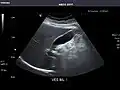

Abdominal Ultrasound (Full Exam)

STRUCTURED REPORT

(Technique: Transabdominal ultrasonography; Device: Toshiba Aplio XG)

Liver: Diffusely homogeneous and normal in echogenicity. No focal mass or contour nodularity. No intrahepatic biliary ductal dilatation.

Portal Vein: Patent main portal vein.

Gallbladder: No stones, wall thickening, or pericholecystic fluid.

Common Bile Duct: Nondilated measuring 1.3 mm at the level of the porta hepatis.

Pancreas: Visualized portions unremarkable.

Spleen: Normal in size.

Kidneys: Right and left kidneys measure 11.5 cm and 12 cm in length respectively. No hydronephrosis. Small left lower pole kidney cyst.

Ascites: None.

Aorta: Visualized portions normal in caliber, 16 x 15 mm.

IVC: Normal.

IMPRESSION:

Normal abdominal ultrasound.